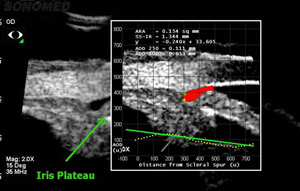

Вдобавок к возможности получать эхограммы высокого разрешения для различных структур угла передней камеры, ультразвуковой биомикроскоп VuMAX® включает в себя незаменимый другими методиками программный пакет инструментов для диагностики глаукомы, такие как оценку рецессии амплитуды угла передней камеры, оценку толщины радужной оболочки, исследование структуры основания радужной оболочки, расположение цилиарного тела и многое другое.

Возможность увидеть глаз в динамике, а в частности, расположение и взаимодействие структур переднего отрезка глаза в процессе аккомодации в зависимости от освещенности, может оказаться очень важным инструментом в диагностике.